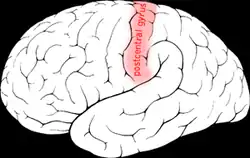

| Postcentral gyrus | |

Postcentral gyrus of the human brain | |

In neuroanatomy, the postcentral gyrus is a prominent gyrus in the lateral parietal lobe of the human brain. It is the location of the primary somatosensory cortex, the main sensory receptive area for the sense of touch. Like other sensory areas, there is a map of sensory space in this location, called the sensory homunculus.

The lateral postcentral gyrus is bounded by:

- medial longitudinal fissure medially (to the middle)

- central sulcus rostrally (in front)

- postcentral sulcus caudally (in back)

- lateral sulcus inferiorly (underneath)

The postcentral gyrus includes Brodmann areas 1, 2, and 3. Brodmann area 1 occupies the apex of the postcentral gyrus.